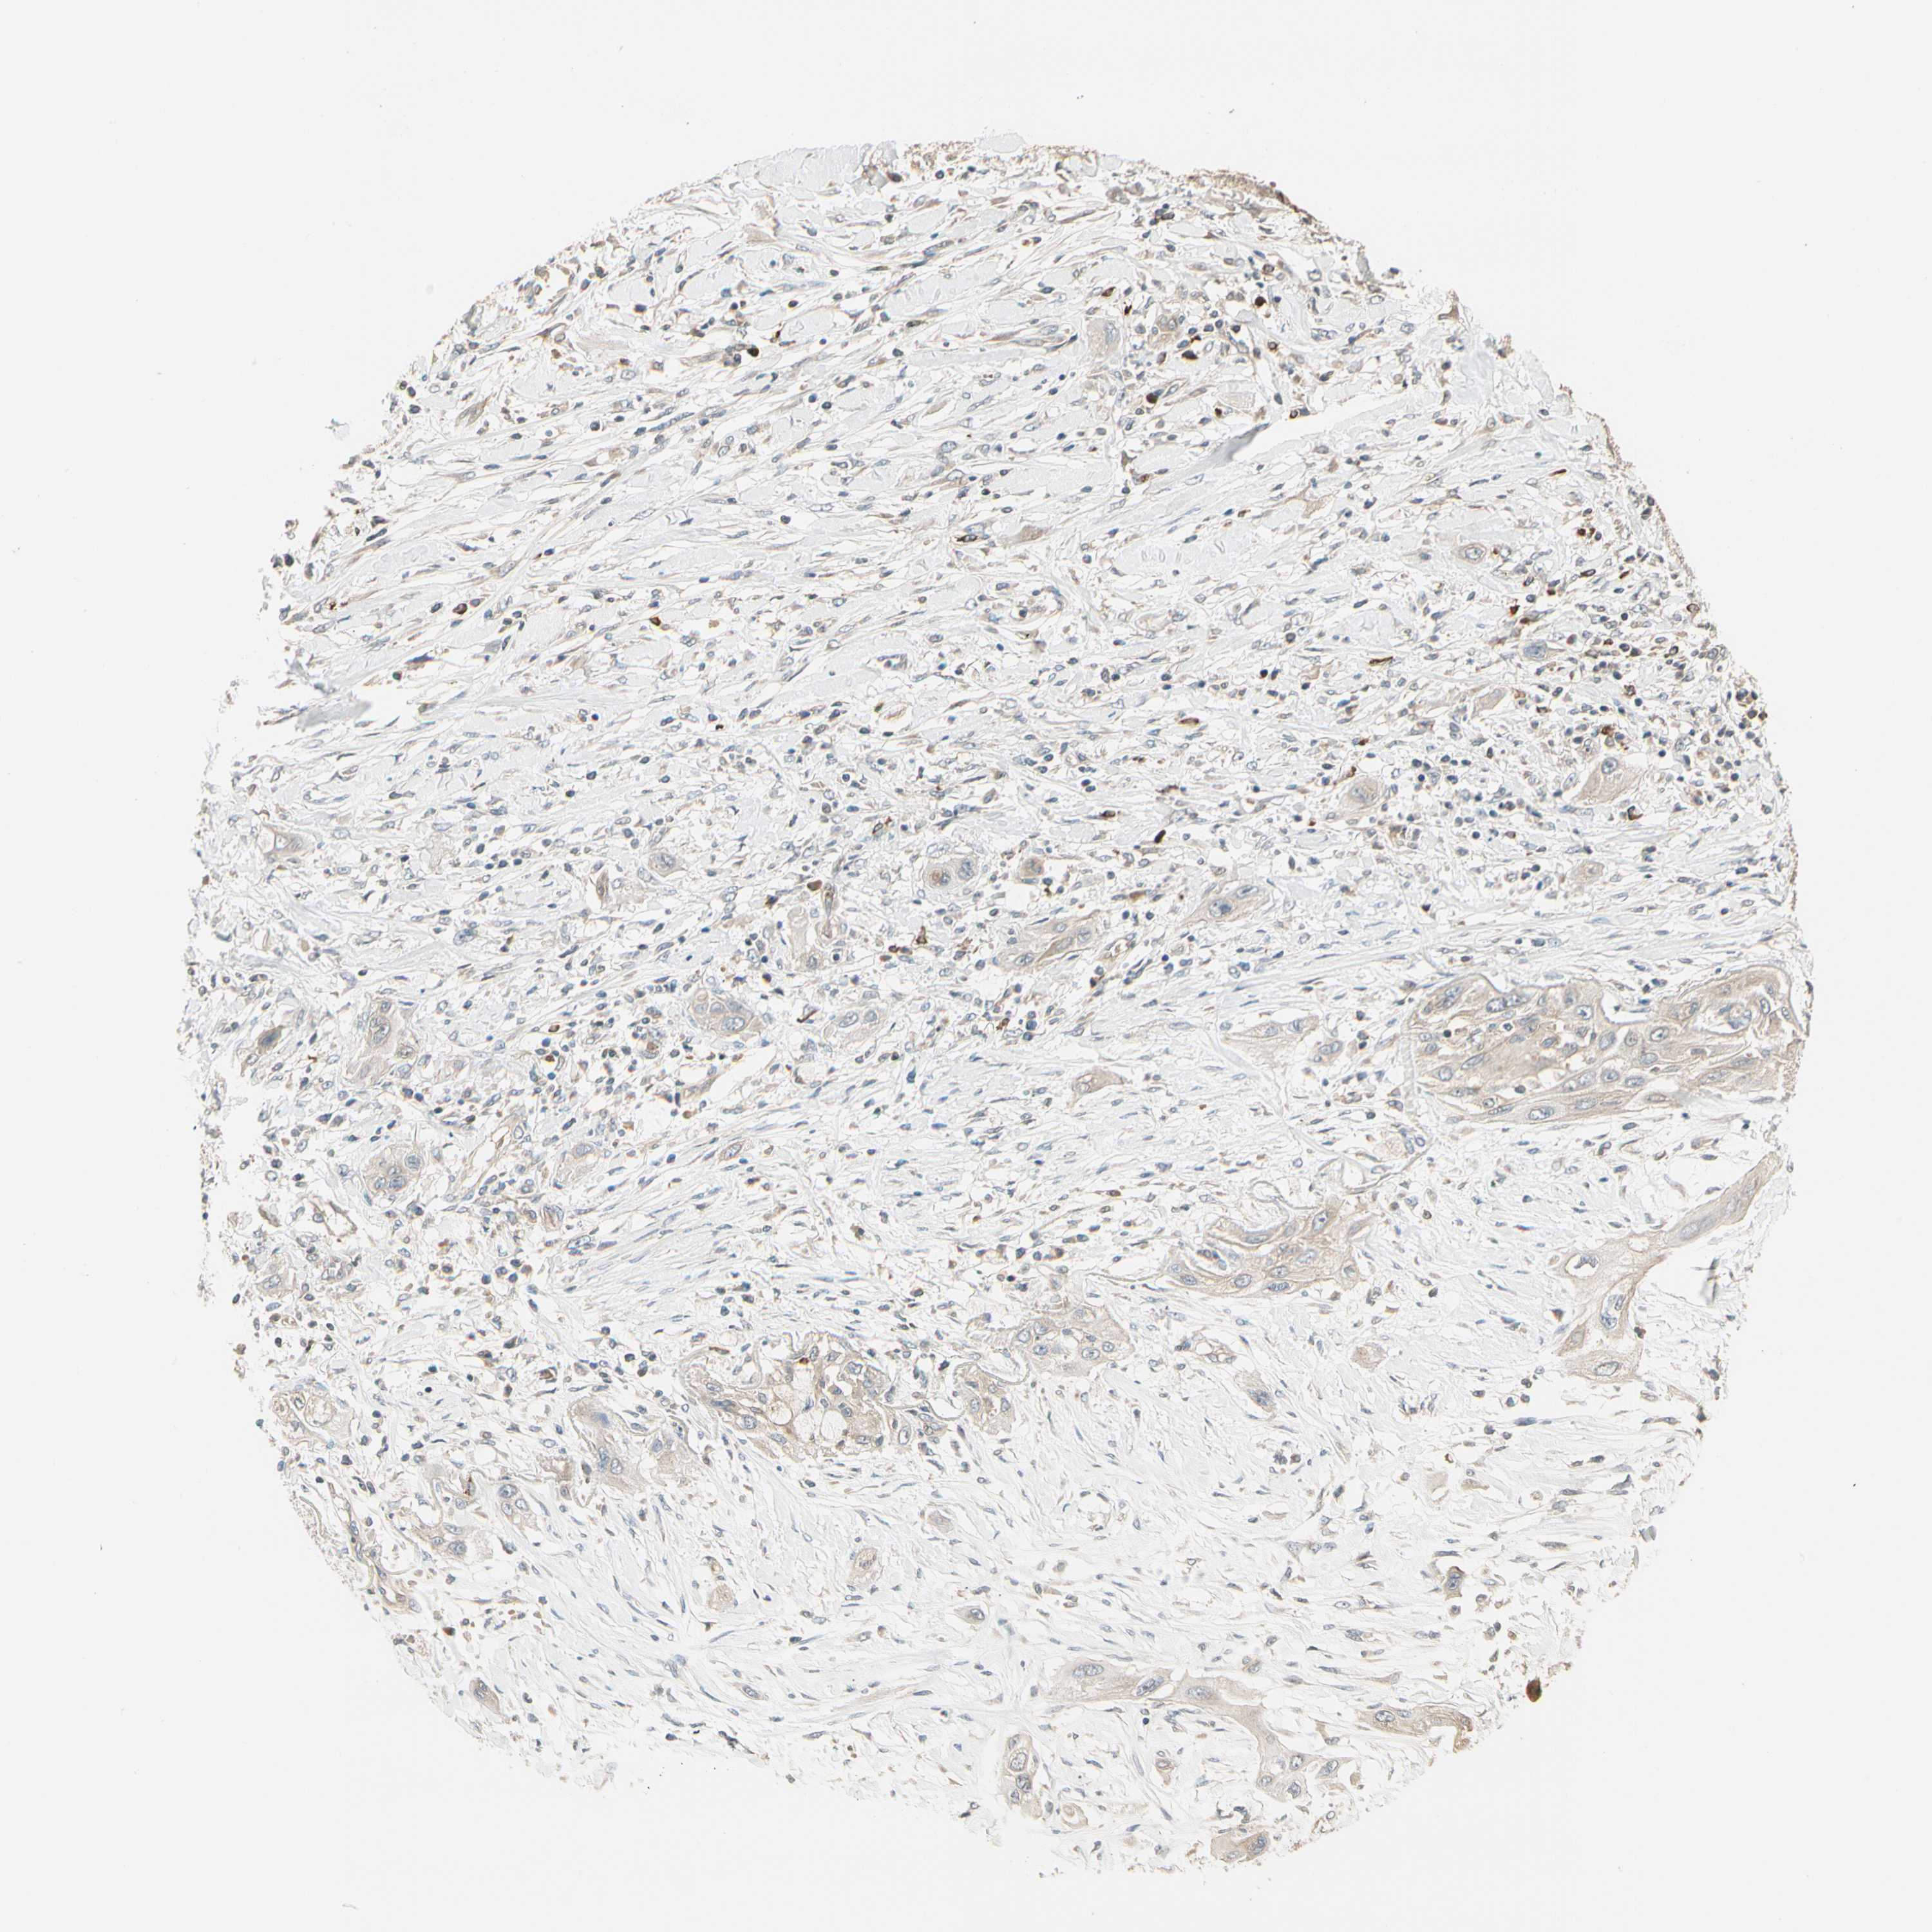

TNFRSF21

CANCER LUNG CANCER Show tissue menu